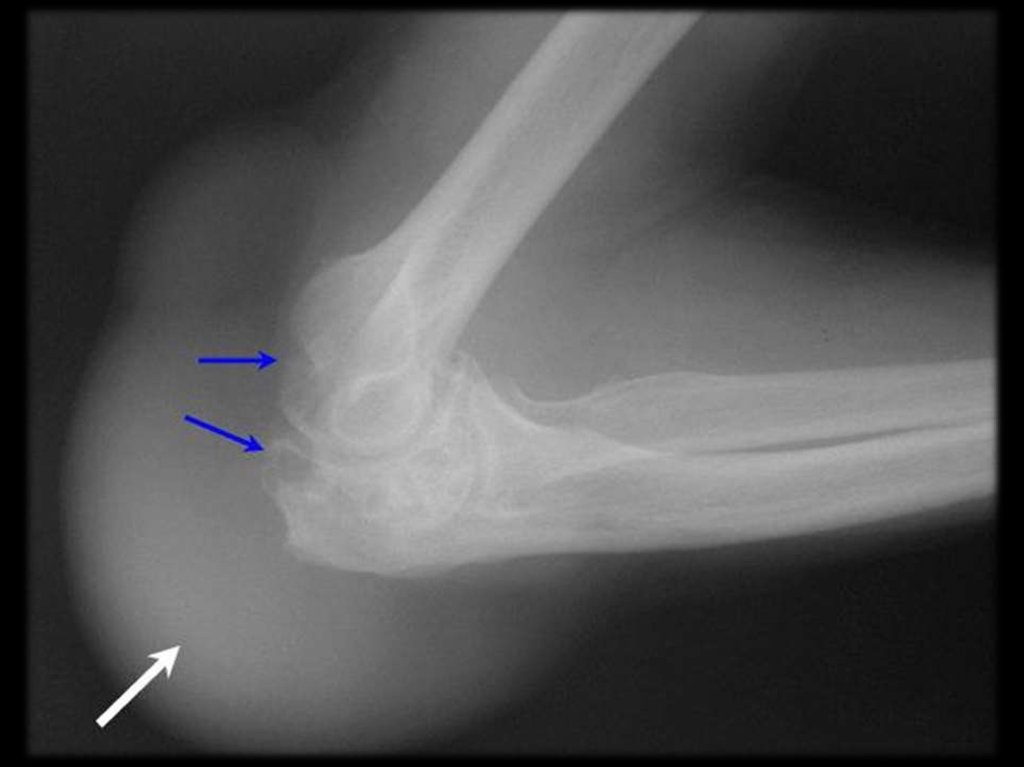

Динамика рентгенологических изменений в

области суставов при хроническом сифилисе

Сифилитический артрит левого коленного

сустава, контрактура